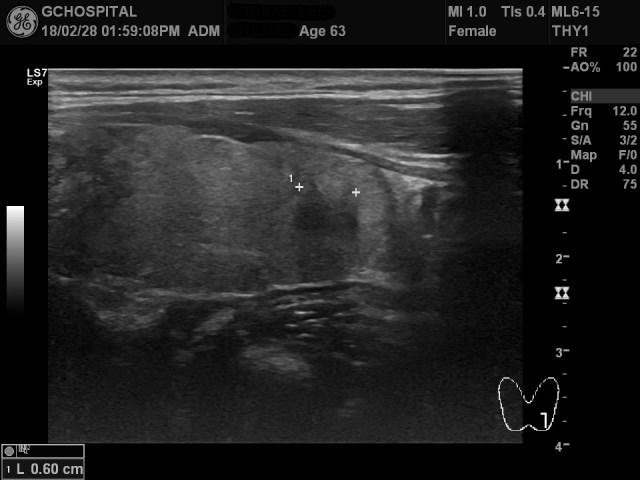

위 영상은 목 앞쪽에 뭔가가 만져진다고 하셔서 내원한 63세 여자환자의 초음파영상입니다. 좌엽 아랫쪽에 캡슐이 존재하지 않지만, 윤곽은 알아볼 수 있는 결절이 있고, 해당 결절 내부에는 후방에코음영이 진하게 관찰되는 병변이 있습니다.

이와 같은 양상의 결절성 병변들이 양측 갑상선엽에 5-6개 정도 흩어져서 보였고, 이러한 결절은 갑상선윤곽을 돌출시키면서, 결절 내부에 공통적으로 진한 후방에코음영을 보였습니다.

후방에코음영이 있을때는 당연히 석회화(calcification)를 생각할 수 있지만, 에코가 반사되어 하양게 보이는 부분이 전혀 없었기 때문에, macrocalcification인지, 아니면 미세석회화(microcalcification)이 모여있는 것인지를 구별할 수 없었고, 단지 석회화음영이라는 것 정도만 특정지을 수 있었습니다.